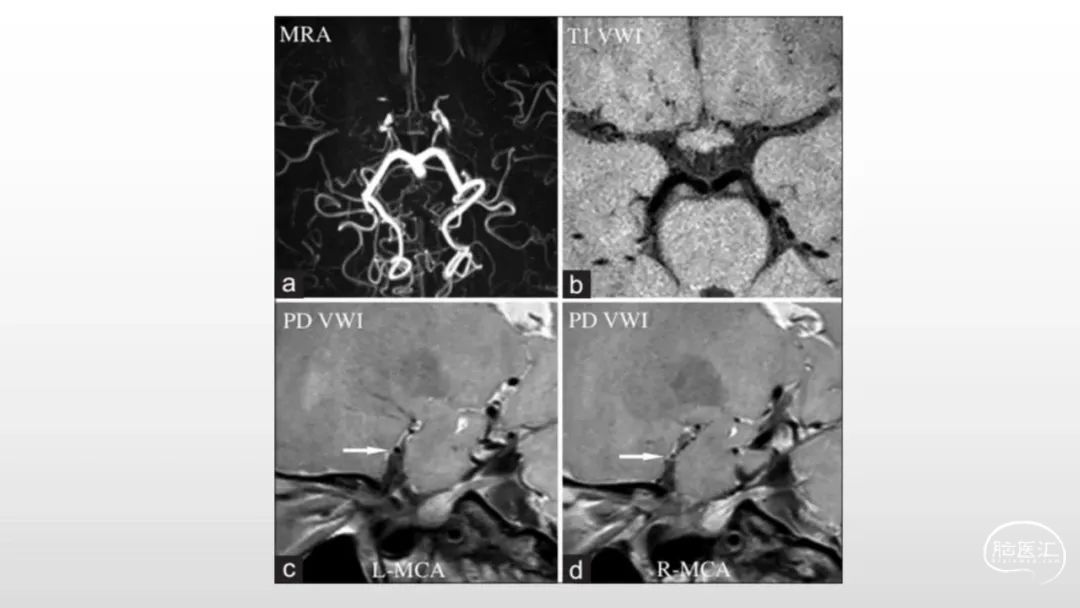

颅脑影像诊断基础知识讲座:《脑血管病》之出血、血管畸形、动脉炎及神经卡压